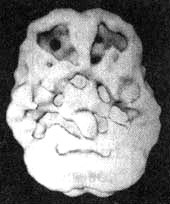

Мозг Карла. Алкогольная зависимость

Иллюстрация к книге — Измените свой мозг - изменится и жизнь! [i_089.jpg]

Трехмерное изображение нижней поверхности. Обратите внимание, что мозг выглядит сморщенным, особенно в области префронтальной коры и височных долей.